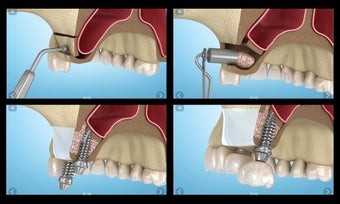

إذا كنت متخصصًا في طب الأسنان أو مريضًا، فقد تساعدك هذه الأداة في تعلم علاجات الأسنان.

تم إنشاء هذا التطبيق بواسطة أليكس ميت للأطباء الأسنان وطلاب طب الأسنان والمرضى. كما يمكن استخدامه أيضًا من قبل المهنيين الطبيين الآخرين.

يستند التطبيق على مبدأ عرض الشرائح. يحتوي كل موضوع على 3-9 صور. يمكن عرض صور أي موضوع في أي وقت.